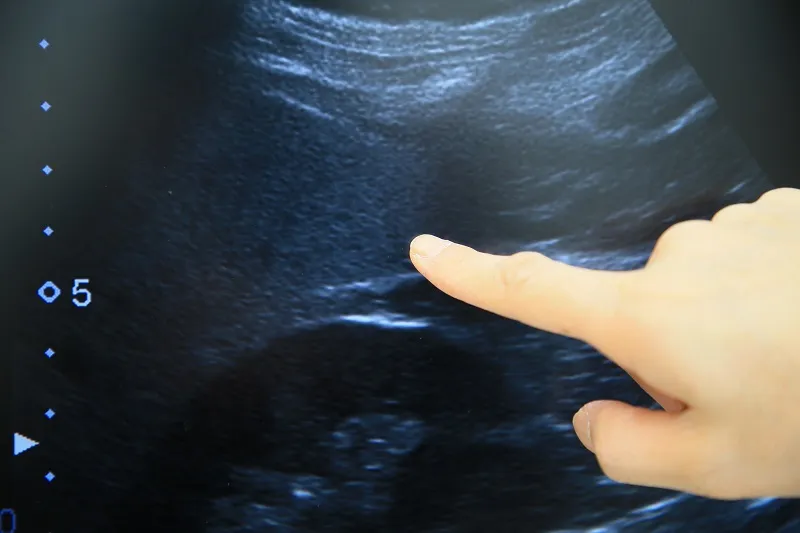

肝障害を認める場合、原因は脂肪肝以外にも複数考えられ、B型肝炎など除外すべき疾患は多岐にわたるので注意が必要です。肝障害を認めた場合は脂肪肝と決めつけることなく、消化器内科で詳しい採血や腹部エコー検査などを行い、脂肪肝の診断をしっかり確実につけることが前提となります。